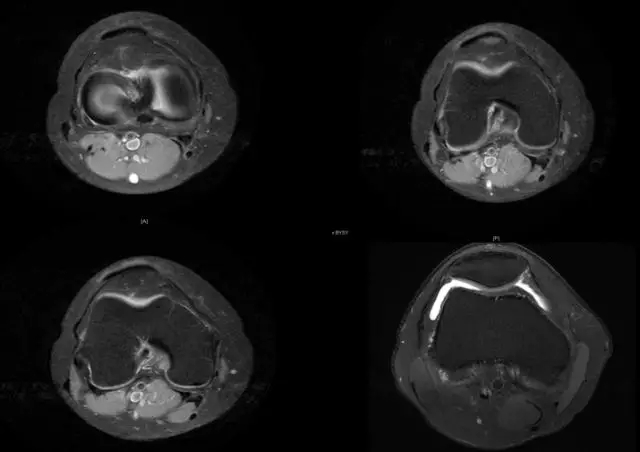

Blumensaat 角(-1.6度)

大于9-15度视为异常

前交叉韧带与胫骨平台角度(56度)

小于45-50度视为异常

后交叉韧带折弯度

弧度:0.19厘米,角度:114-123度